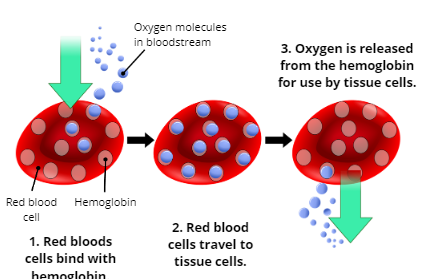

Oxygenation

the process of supplying oxygen to the body’s tissue cells

Explain the Process of Oxygenation

1. Oxygen molecules in the bloodstream enter red blood cells and bind with hemoglobin

2. Red blood cells travel to tissue cells

3. Oxygen is released from the hemoglobin for use by tissue cells